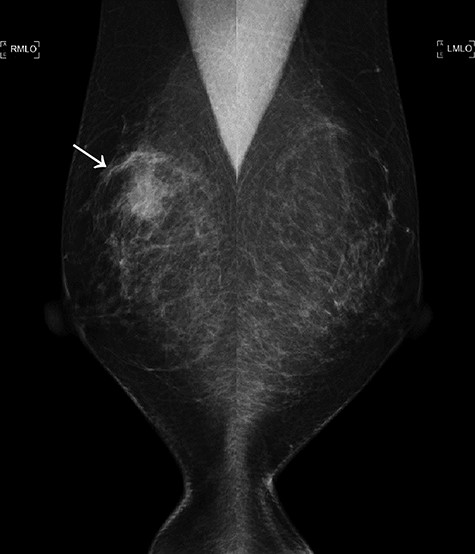

A total of 17 months after completing the adjuvant treatments, she noticed a mass in her left breast. Imaging analyses displayed a 15 mm mass in her left breast and multiple swollen axillary LNs (Figs 4 and 5A). Histopathological analysis of a CNB demonstrated metaplastic carcinoma (Fig. 6). The intrinsic subtype was TNBC with a Ki-67 score of 90%.

The second mammogram. The mammogram displaying a well-defined borderline high-density mass in the left upper lateral region (arrowhead).